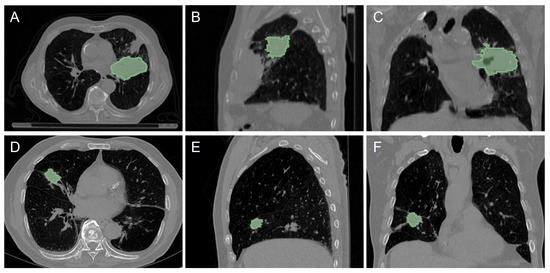

A total of 403 patients from LUNG1 and 130 patients from LUNG2 were thus finally considered. More details about CT images and patients’ clinical information are summarized in Table 1, whereas illustrative examples of both datasets are shown in Figure 1. Additionally, patients were dichotomized into non-survivor and survivor based on their overall post-operative survival time, with a cut-off of two years, similar to the median survival time for these patients [9,35].

Figure 1.

Examples of CT images and tumor volumes (marked with a green area) from LUNG1 (upper row) and LUNG2 (lower row) datasets: axial (A,D), sagittal (B,E), and coronal (C,F) views.